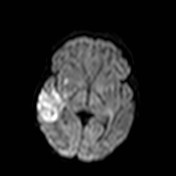

33.a.US examination, coronal view. On the right temporal lobe a small echogenic area can be seen.

Image

33.b. MRI, axial view, diffusion sequence. Right sided, 3.5 cm area with restricted diffusion. Acute infarct in the parieto-temporal region. (SE, MRKK, with the courtesy of dr. György Várallyai).

33 a-b. Cerebral infarct, newborn.